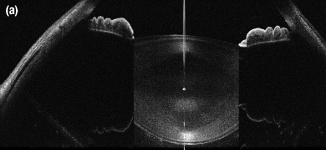

An Image of the Anterior of the Eye Taken with the SLD830S-A10 in a Modified Ganymede System

SLD830S-A10

830 nm SLD, Gain Ripple: ≤0.15 dB

OCT用途例

それぞれの画像の組織内深度は6.2 mmで、36 kHzのA-スキャンレートで撮影されています。